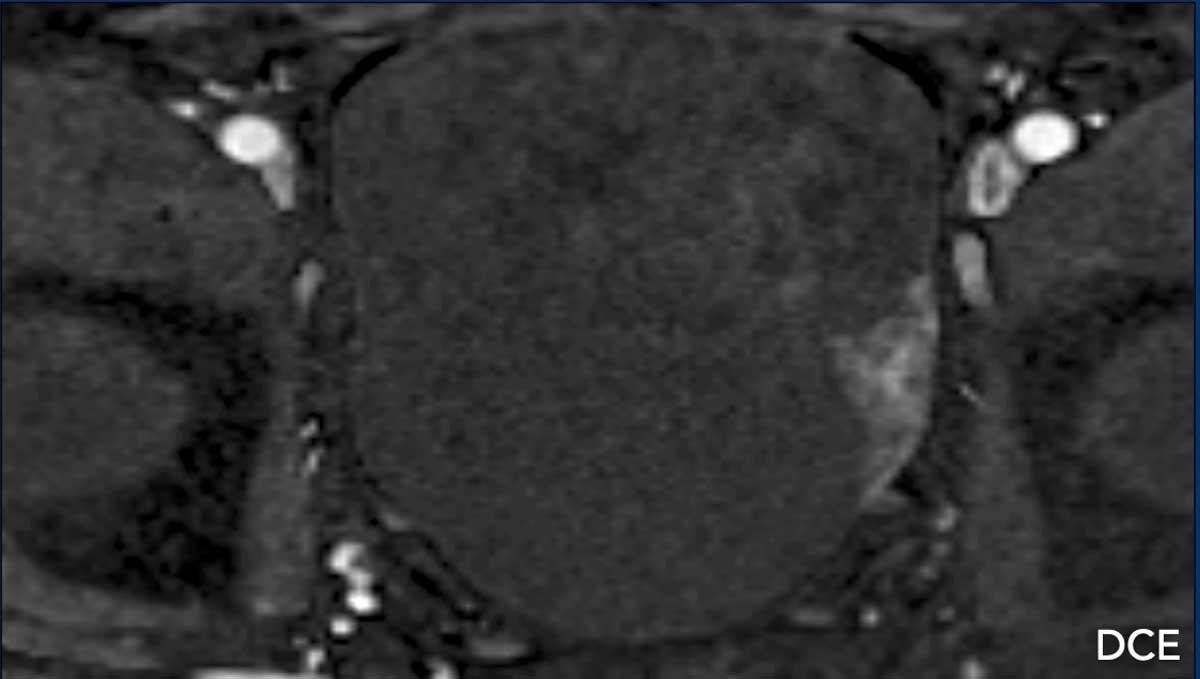

Khối u có ngấm thuốc.

Trên chuỗi xung DCE, lớp trong tiếp giáp với tổn thương cũng có ngấm thuốc.

Tiếp tục xem các hình ảnh khuếch tán…